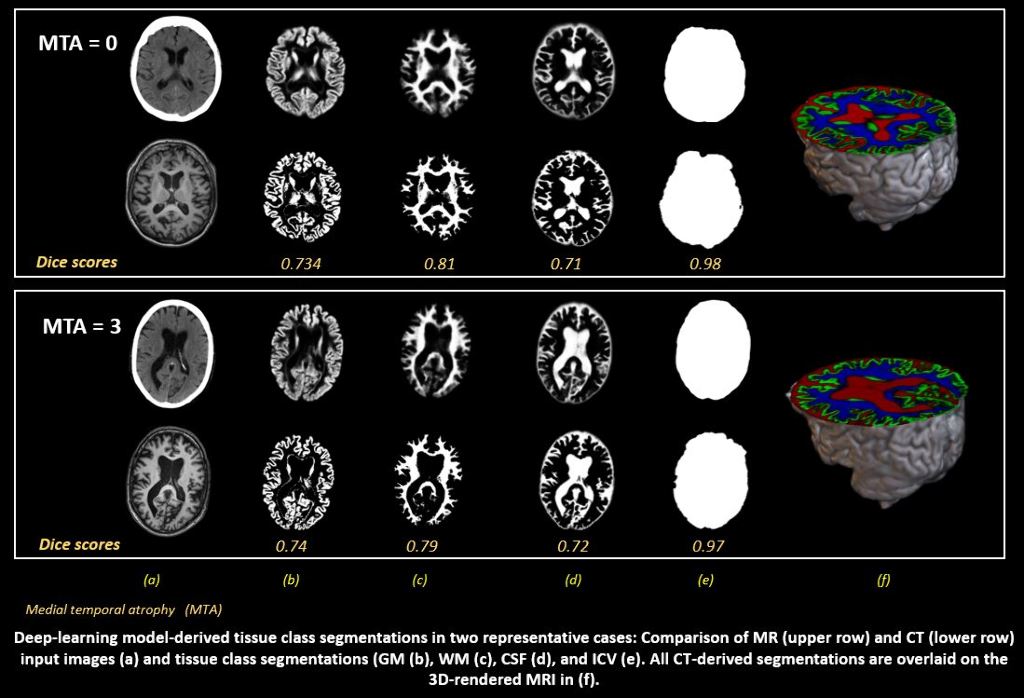

Brain computed tomography (CT) and blood sampling are two routinely performed examinations in the clinical assessment of neurodegenerative diseases. We aim to evaluate the diagnostic performance of automated CT-based volumetry, derived with a novel deep-learning approach, and plasma-based neurofilament light chain (NfL).

A first dataset was included from the Gothenburg H70 Cohort of which 734 participants (age= 70.42±2.6 years, 52.6% female) had paired CT and T1-weighted MRI scans. Grey matter (GM), white matter (WM), cerebrospinal fluid (CSF) and intracranial volume (ICV) segmentations were derived from MRI. A U-Net was trained on these to automatically predict the same tissue classes from CT, which were compared with MRI-segmentations for volumetric, spatial and shape similarity. Associations between CT-derived GM volumes (controlled for ICV), plasma NfL and mini mental state examination (MMSE) were tested using linear regressions. A second dataset including 300 participants with paired CT and MRI of which 30% had a clinical dementia diagnosis was included from the NUS MACC to validate diagnostic performance of the acquired measures.

In the H70 Cohort, high volumetric correlations and continuous Dice scores were observed between CT- and MRI-derived GM, WM, CSF and ICV. Lower CT-derived GM volumes were significantly correlated with higher plasma NfL (p=0.005) and lower MMSE scores (p= 0.001).

Preliminary results demonstrate clear potential for automated CT-derived volumetry in the assessment of neurodegeneration. Future work will improve the applied methodology, explore associations with visual assessments of GM atrophy, and the concrete diagnostic potential of both CT-volumetry and plasma NfL.